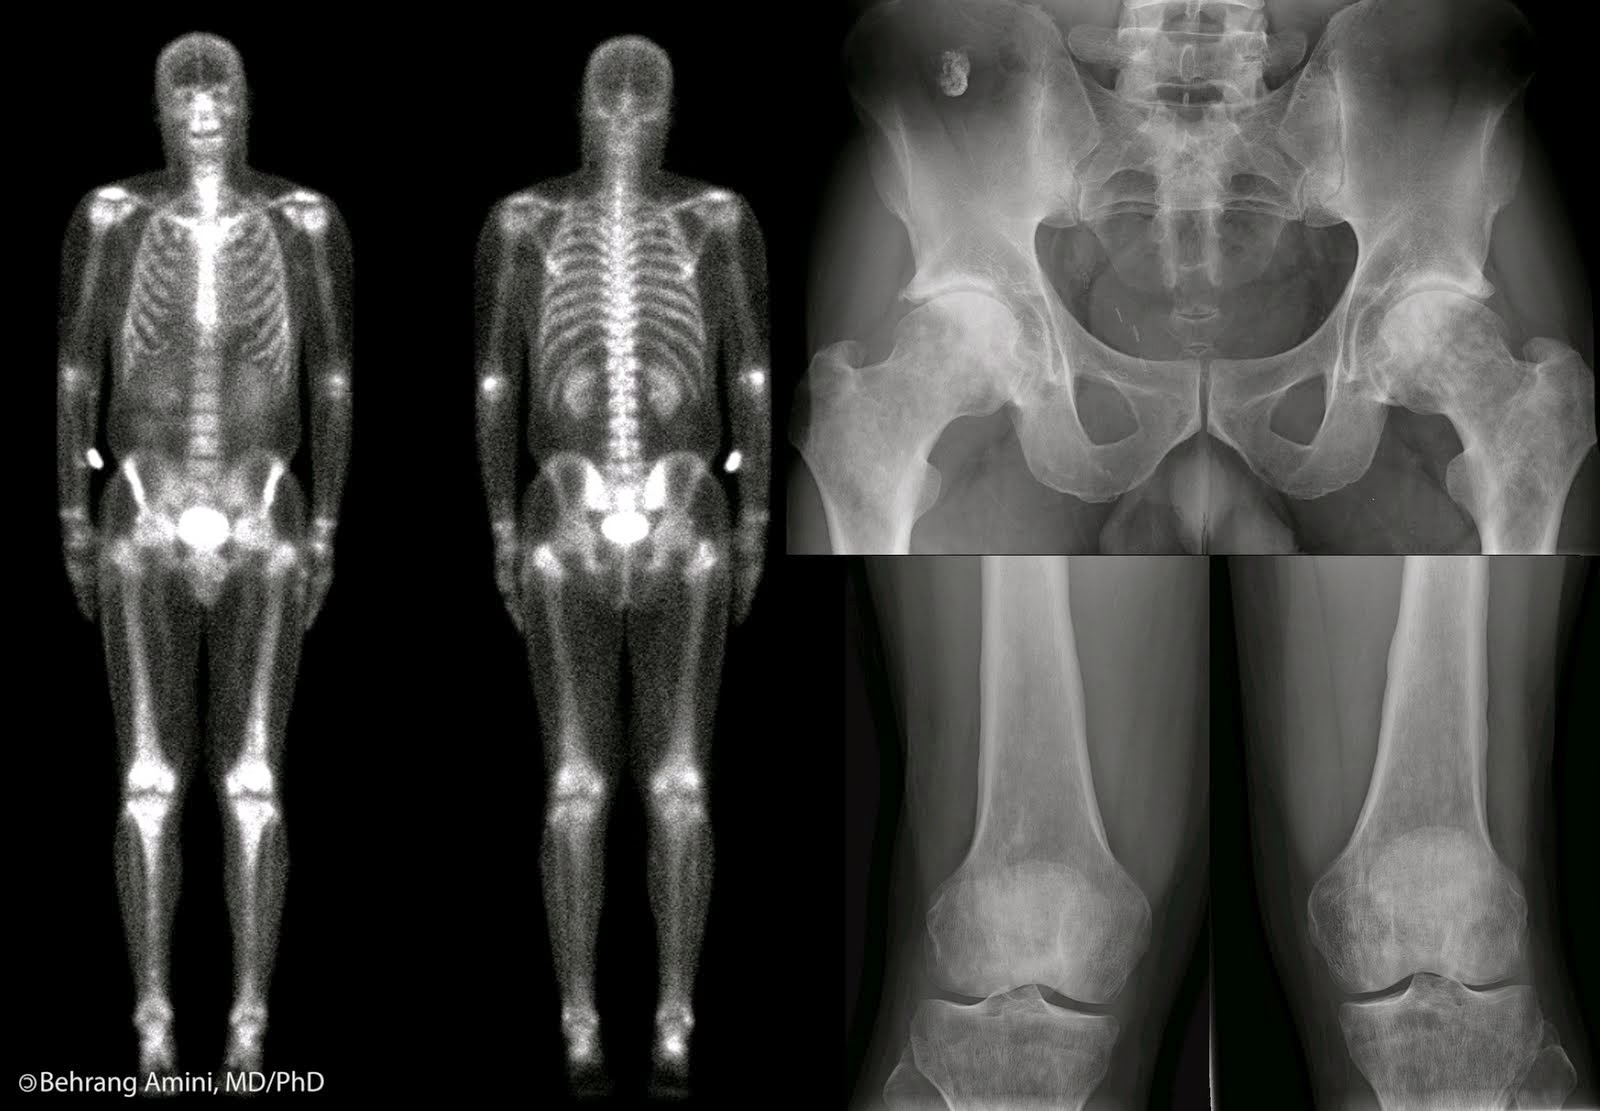

O estudo das radiografias nos auxilia no diagnóstico de uma gama variada de patologias. Os exames simples como radiografias de tórax e seios da face na pneumologia, radiografias de todo o sistema esquelético para a ortopedia, radiografias do abdome e contrastadas dos seus órgãos internos, como rins, estômago, intestinos, etc, exames estes aplicados na clínica médica, cirurgia e urologia. É preciso destacar ainda, os estudos de vasos nas arteriografias para a cardiologia e cirurgia cardiovascular, exemplifica o especialista.